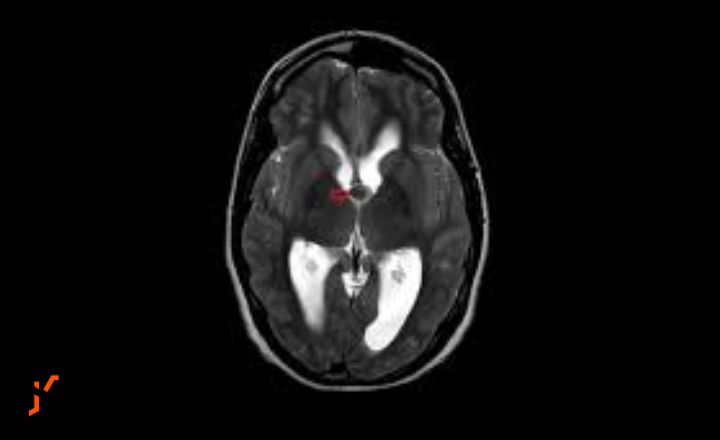

Accurate diagnosis of colloid cysts relies heavily on advanced neuroimaging techniques that can visualize the brain’s internal structures with remarkable precision. Magnetic resonance imaging, or MRI, has become the gold standard for identifying and characterizing these cysts, offering superior soft tissue contrast that allows neurologists and neurosurgeons to determine the cyst’s exact size, location, and relationship to surrounding structures.

The appearance of colloid cysts on MRI can vary depending on their protein content, typically showing as round or oval masses in the anterior third ventricle near the foramen of Monro. Computed tomography scans may also be used, particularly in emergency situations, though they provide less detailed information about cyst characteristics. Beyond simply identifying the cyst’s presence, imaging helps clinicians assess whether hydrocephalus has developed and evaluate the degree of ventricular enlargement. Serial imaging over time can track cyst growth rates and help determine when intervention becomes necessary, making these diagnostic tools essential not just for initial diagnosis but for ongoing monitoring and treatment planning.